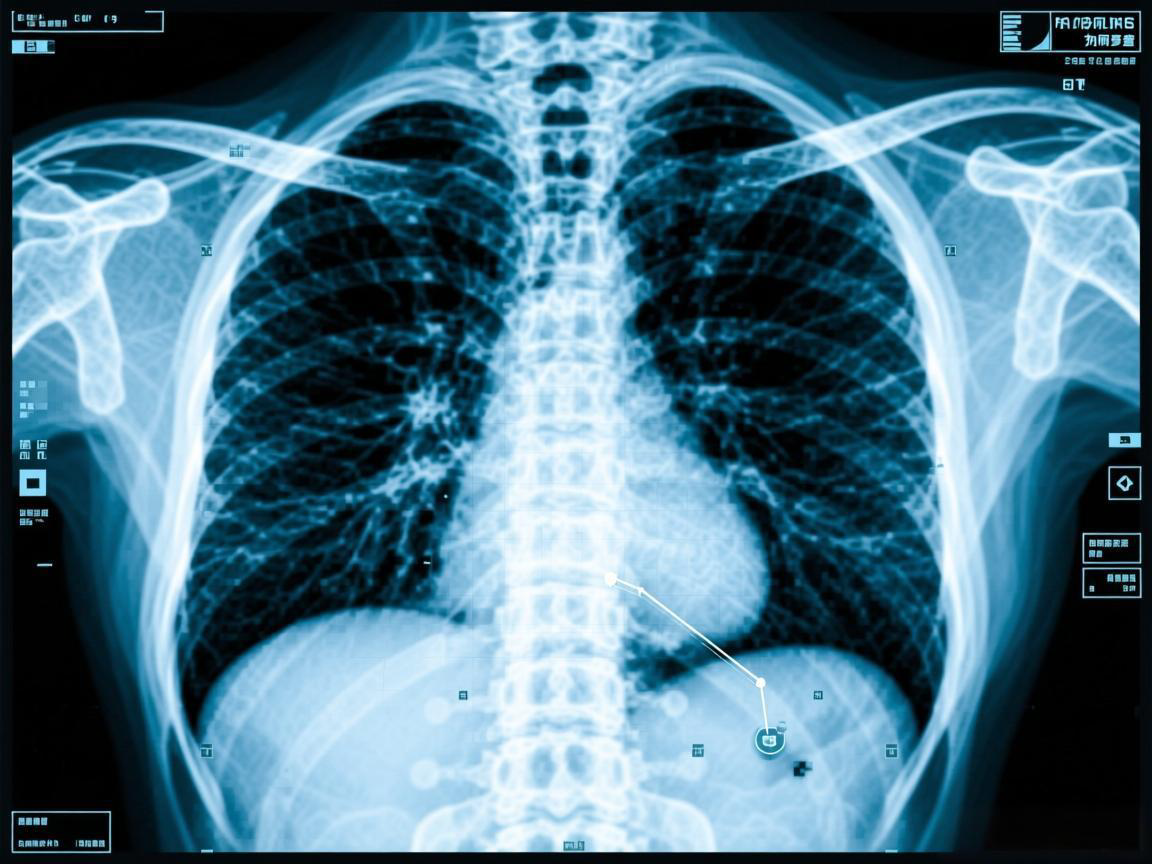

X光CTMRI区别及选择指南

骨科就诊时,X光用于初筛骨折、关节脱位等骨骼问题;CT能清晰显示细微损伤并提供三维结构;MRI则擅长观察脊椎、椎间盘、肩袖等软组织病变,是诊断骨骼外疾病的首选。根据症状选择相应检查,可快速明确诊断。

X光CT核磁:为何需多查?

患者常疑惑为何需同时做X光、CT和核磁共振。其实三者视角不同:X光看整体外观,CT察内部结构,核磁显电路管路。如同观察楼房需多角度检查,综合运用才能精准诊断疾病,制定最佳治疗方案。